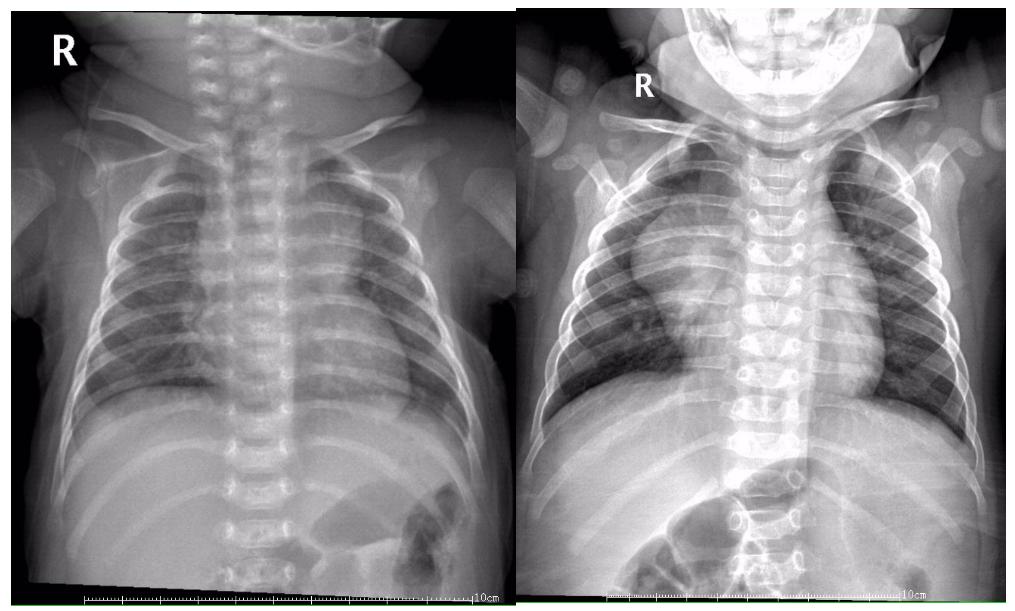

近日,有几个呼吸系统疾病患儿的胸片,引起年轻的规培医师的疑问,如下图1、图2所示:

图1示:左侧胸片为右上肺炎征象;右侧胸片示胸腺影

图2示:左侧胸片为右上肺炎征象;右侧胸片示胸腺影

以上2组图片,你能区分哪张是肺炎患儿,哪张是正常胸腺影像吗?

图1、图2左图均显示右上肺可见大片状、云雾状模糊影,结合患儿临床表现如发热、咳嗽、听诊可闻及呼吸音减低,出现痰鸣音或细湿性啰音等可明确为肺炎征象;

图1右图显示单侧致密均匀三角形,内缘与纵膈相连,下缘位于水平叶裂位置,边缘均清晰锐利。图2右图显示致密均匀,内缘位于纵膈内,外缘自内上斜向外下延伸,虽然因肺门影影响而似乎边缘不够清晰,放射科医师可通过不同层次的显现,可明确观察到系同一组织的征象。

2组胸片表现极为相似,正所谓:两兔傍地走,安能辨我是雌雄?这就要我们临床工作者,尤其是影像学科的年轻医师了解和熟悉婴幼儿胸腺的影像表现了。